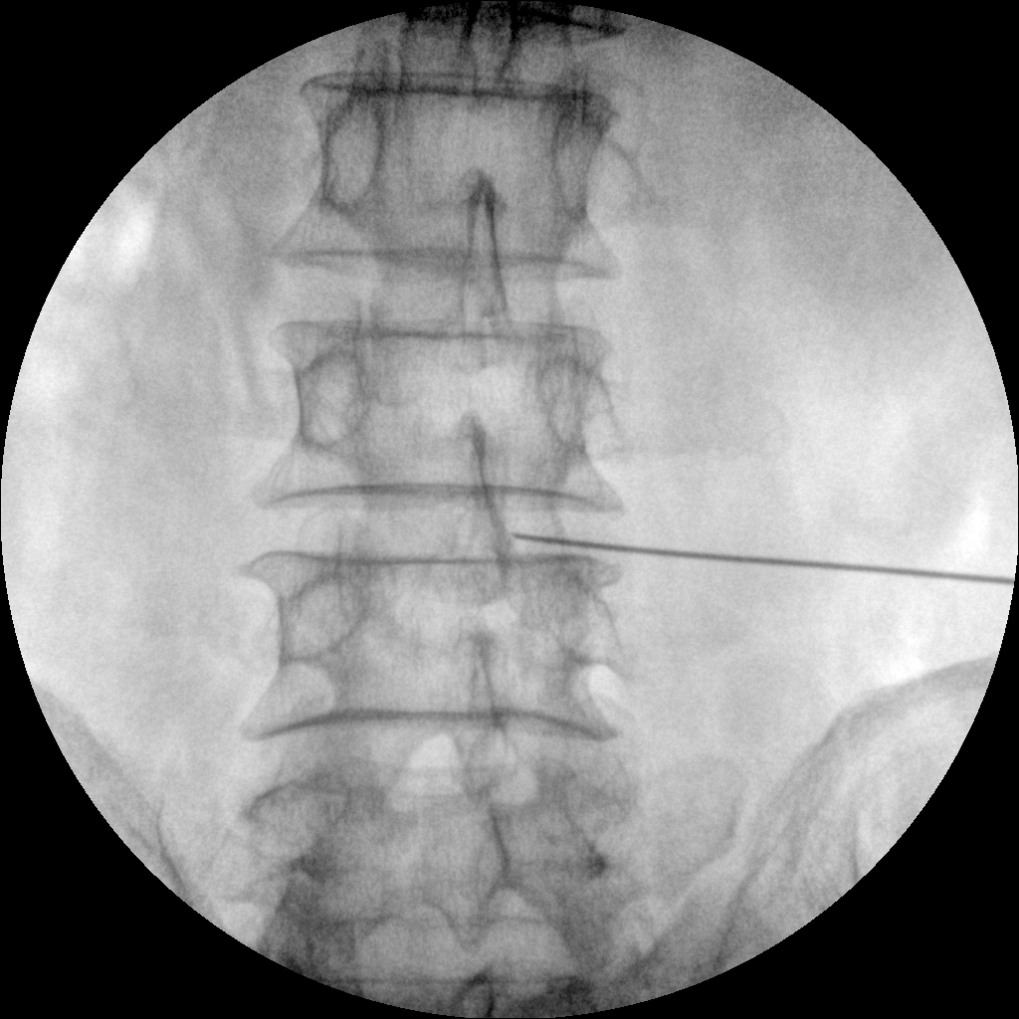

Clinical picture

临床图片